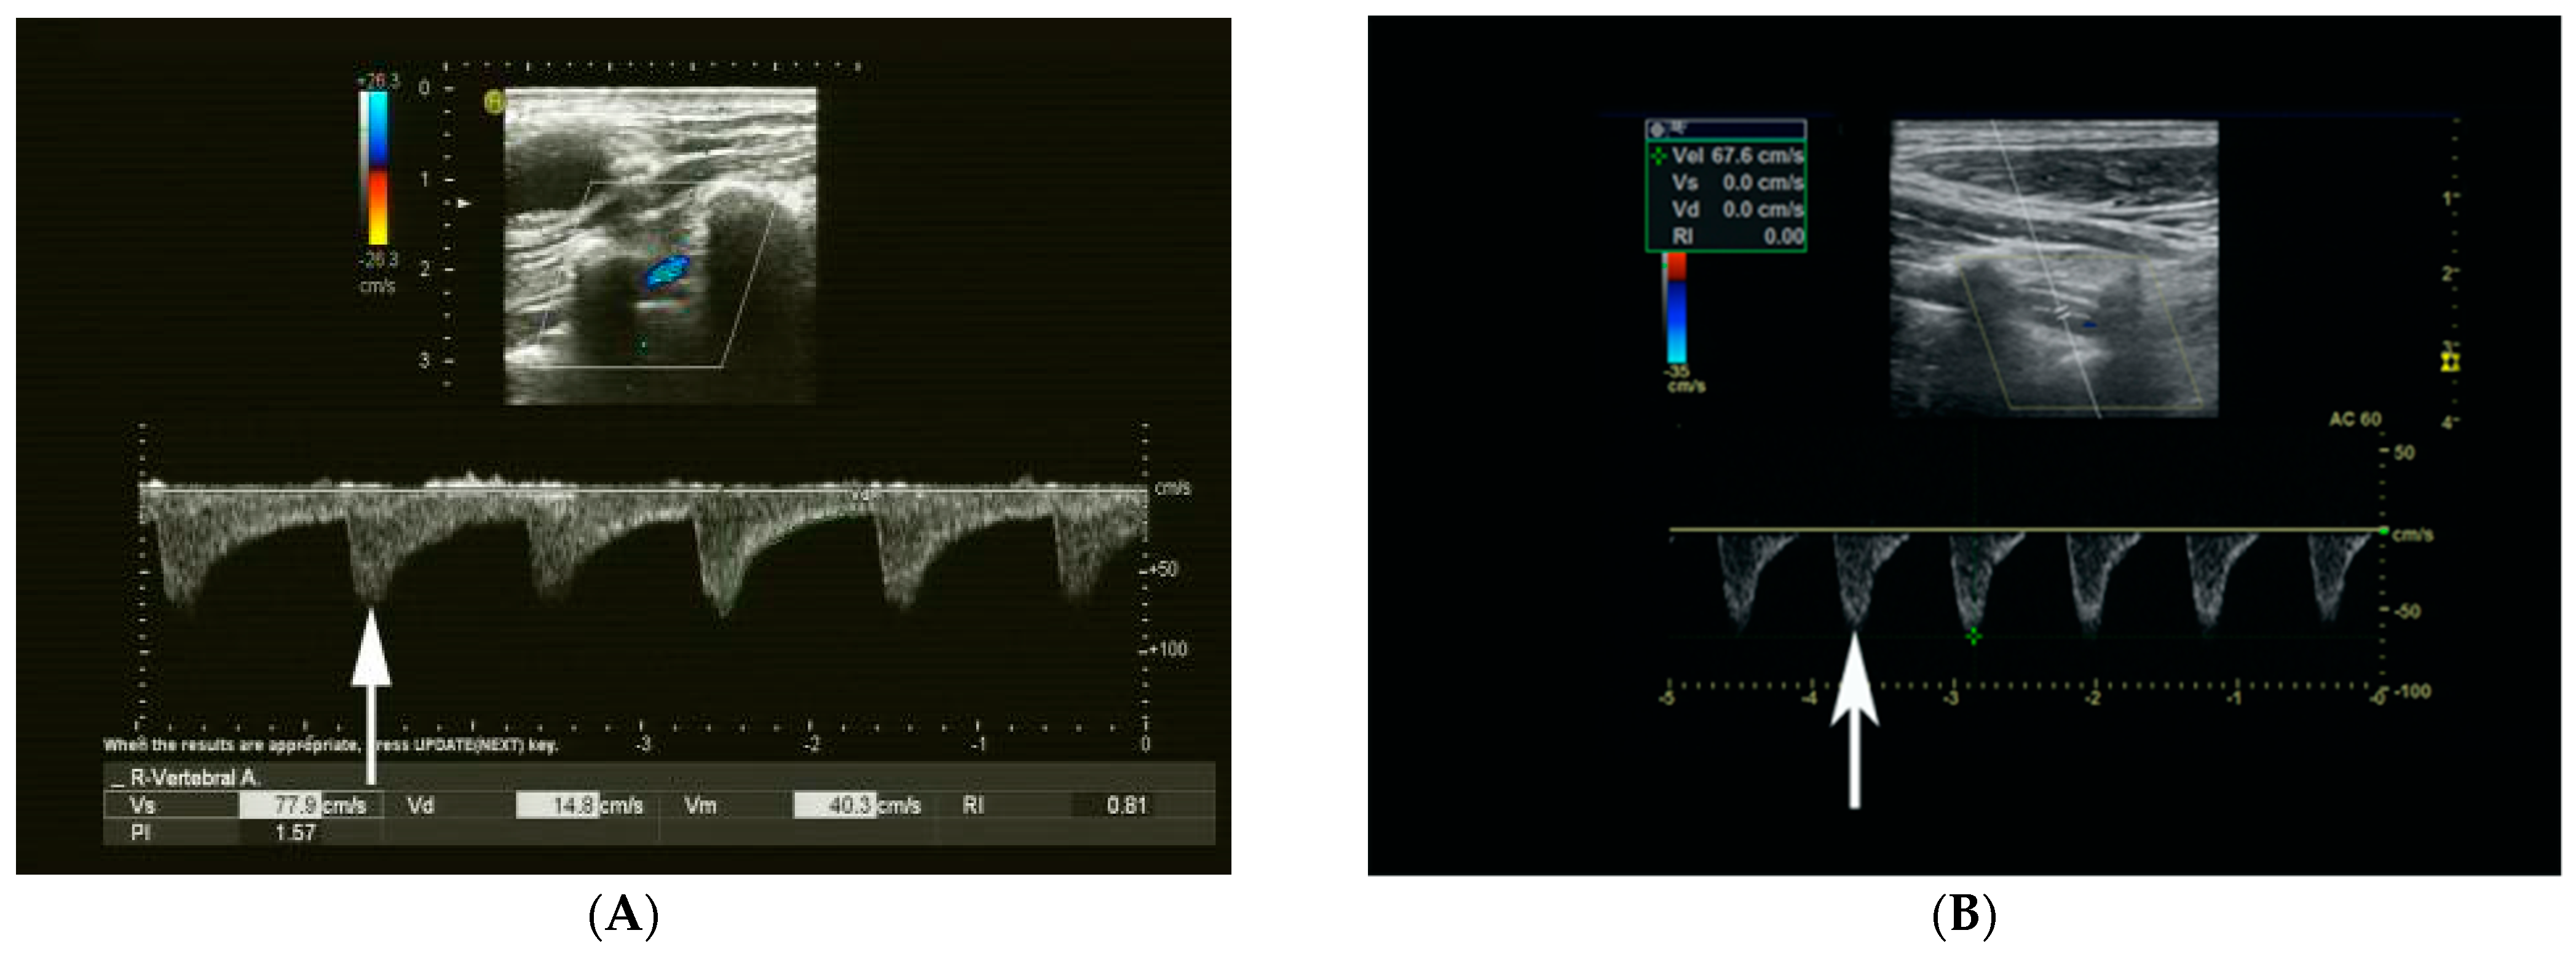

3.2. Correlation of CRF Waveform and VA Parameters with Ipsilateral SA Occlusion or Severe Stenosis